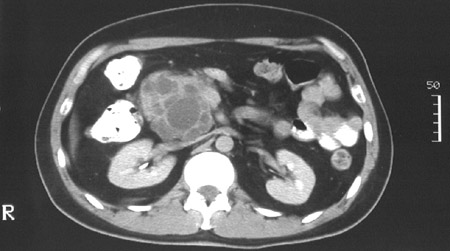

| The abdominal CT scans above and below demonstrate a multiloculated mass consistent with a mucinous cystadenocarcinoma of the head of the pancreas. The bulk of the mass projects downward from the pancreatic head, so the liver and spleen are not seen at this level. |